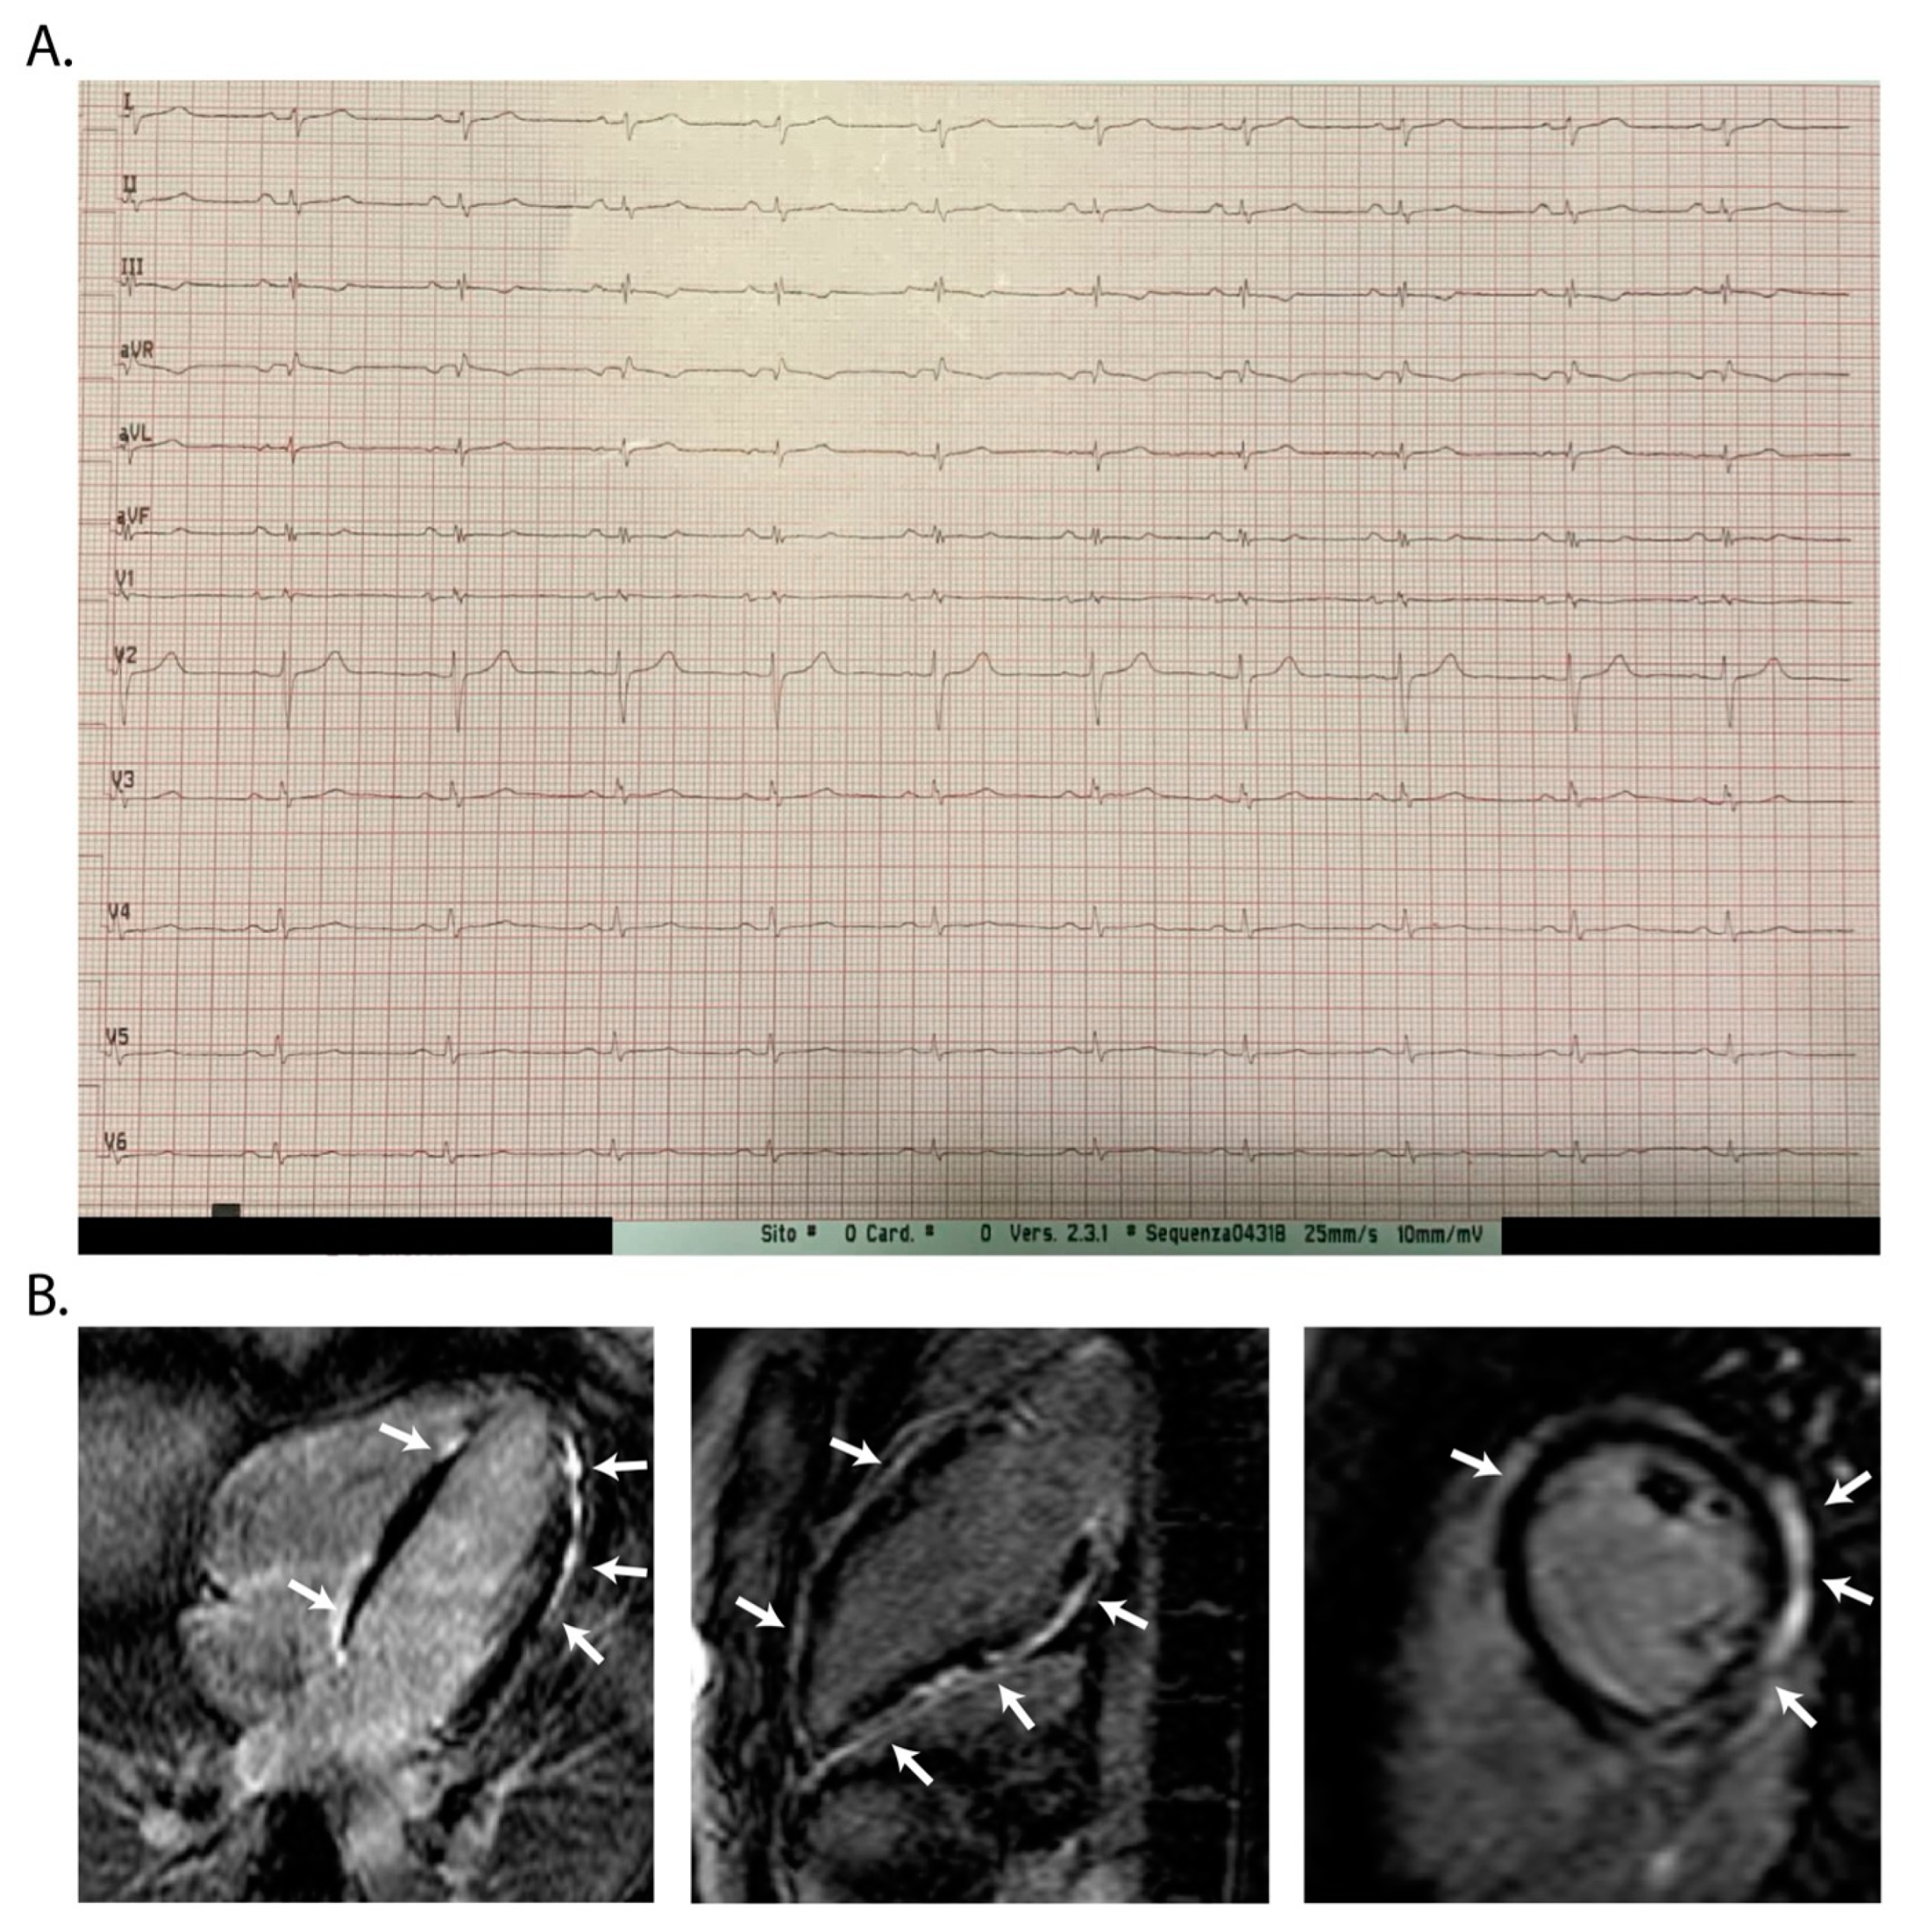

2.4. Twelve-Lead Electrocardiography

- De Lazzari, M.; Zorzi, A.; Cipriani, A.; Susana, A.; Mastella, G.; Rizzo, A.; Rigato, I.; Bauce, B.; Giorgi, B.; Lacognata, C.; et al. Relationship Between Electrocardiographic Findings and Cardiac Magnetic Resonance Phenotypes in Arrhythmogenic Cardiomyopathy. J. Am. Heart Assoc. 2018, 7, e009855. [Google Scholar] [CrossRef]

- Rubino, M.; Scatteia, A.; Frisso, G.; Pacileo, G.; Caiazza, M.; Pascale, C.E.; Guarini, P.; Limongelli, G.; Dellegrottaglie, S. Imaging the “Hot Phase” of a Familiar Left-Dominant Arrhythmogenic Cardiomyopathy. Genes 2021, 12, 1933. [Google Scholar] [CrossRef]

- Monda, E.; Rubino, M.; Palmiero, G.; Verrillo, F.; Lioncino, M.; Diana, G.; Cirillo, A.; Fusco, A.; Dongiglio, F.; Caiazza, M.; et al. Multimodality Imaging in Arrhythmogenic Left Ventricular Cardiomyopathy. J. Clin. Med. 2023, 12, 1568. [Google Scholar] [CrossRef]